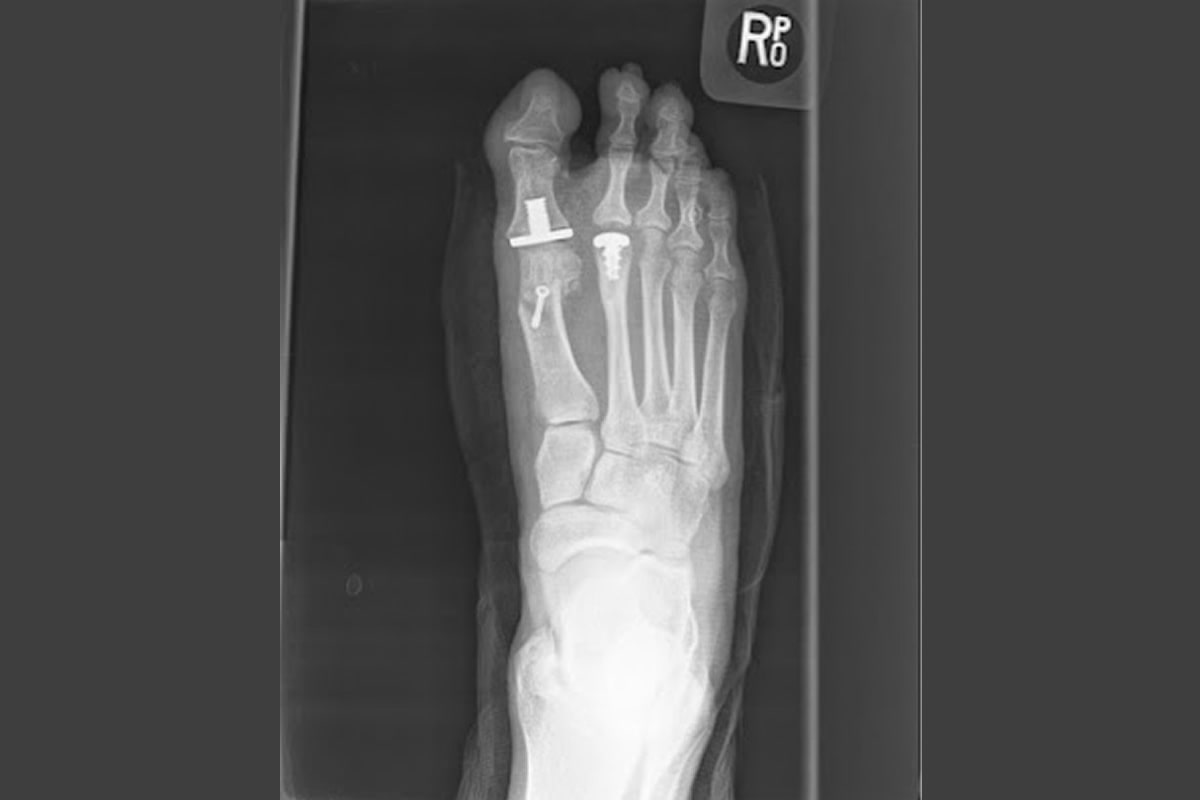

Como cirujanos del pie, consideramos muy importante una exploración clínica, radiodiagnóstica y ecográfica adaptada a cada patología y otras herramientas, como el estudio biomecánico de la marcha, nos permiten realizar un diagnóstico diferenciado, punto de partida clave para elegir la mejor vía de abordaje en cada caso y, en muchas ocasiones, crucial para la detección temprana de afecciones más complejas.

Cirugía Mínimamente Invasiva o Percutánea como Cirugía Abierta del Pie. Utilizando las técnicas más vanguardistas y menos lesivas en cada acto quirúrgico, adaptándolas a la patología de cada paciente.